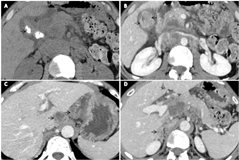

Case Presentation-In our case, the patient 44-years old male, presented with a complaint of pain abdomen and weight loss from the last few months. In the initial investigation, ultrasonography was performed, in which a heteroechic lesion was seen in the gall bladder fossa. He was then advised to get a contrast-enhanced computed tomography (CECT) scan abdomen. CECT scan of the abdomen revealed contracted gall bladder (GB)with asymmetrical circumferential, heterogeneously enhancing thickening (maximum thickness approx.19mm) involving body, neck, and gall bladder fundus with adjacent fat stranding in the GB fossa. GB thickening the body region is seen abutting adjacent inferior hepatic surface with loss of fat planes. Multiple calculi are also seen in GB (Figure 1A&1B).

Multiple heterogeneously enhancing enlarged lymph nodes are noted in the portal, pancreatic, pre-para aortic, aortocaval, and retroperitoneal regions (Figure 1C). Therefore mentioned description signifies Ca GB with lymph node and adrenal metastasis (Stage IV) (Figure 1D).

Figure 1 GB thickening the body region is seen abutting adjacent inferior hepatic surface with loss of fat planes.